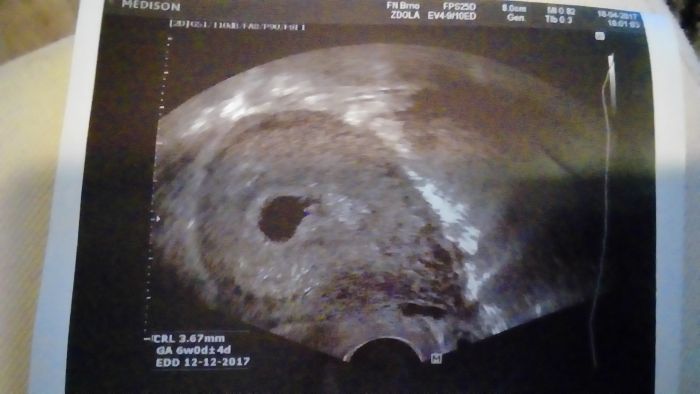

Ahoj holky tak je vše ok a na dobré cestě, srdíčko už tam bylo i nějaká odezva..další kontrola 23.května, tak mě to uklidnilo :-) samo říkal že vyhrané ještě nemám ale to je jasné do toho 12 týdne..

moje fotka ale moc tam toho ještě není vidět